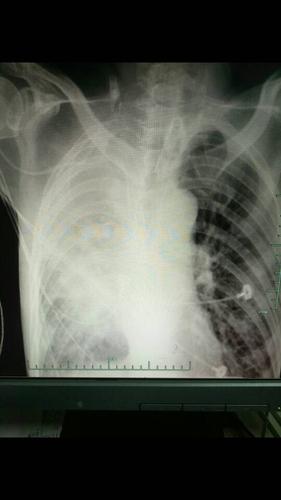

呼吸衰竭入住我院icu,今日出现呼吸急促,费力,听诊右肺呼吸音低,拍